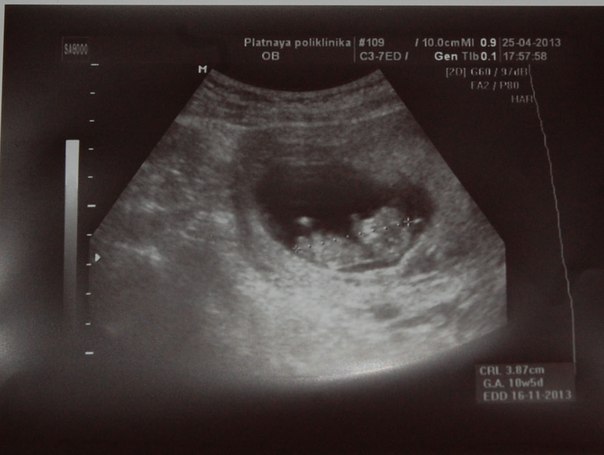

И вот уже 13 недель. Вернее они почти закончились. Решила рассказать как оно...